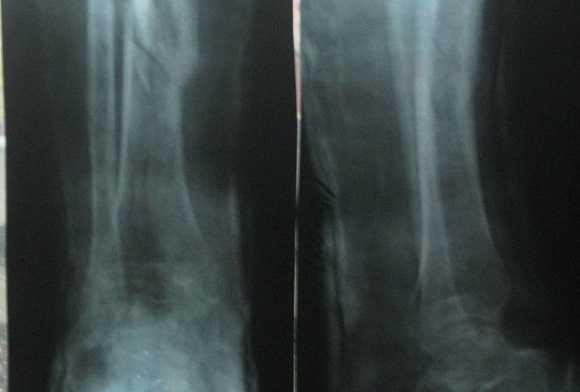

Снимок в данной укладке применяют для диагностики различных заболеваний костей голени и при травмах.

Укладка больного для выполнения снимка. Больной лежит на спине. Ноги вытянуты. Используют кассету размером 24 х 30 см или 30 х 40 см, перекрывая ее вдоль листом просвинцованной резины. Кассету располагают в продольном положении под задней поверхностью голени с таким расчетом, чтобы на снимке получили отображение или оба (при использовании кассеты размером 30 х 40 см), или хотя бы один из метаэпифизов костей голени. Пучок рентгеновского излучения направляют на переднюю поверхность голени в центр кассеты (рис. 429).

Информативность снимка. На рентгенограмме видны обе берцовые кости, их диафизы и метаэпифизы. В области диафизов костей хорошо различаются мозговая полость и корковое вещество. На снимках проксимальных двух третей голени, выполненных на пленке размером 24 х 30 см, отображены головка малоберцовой кости, частично или полностью метаэпифиз большеберцовой кости, а также иногда рентгеновская суставная щель коленного сустава (рис. 430, а). На снимках дистальных двух третей голени выявляются дистальные метаэпифизы большеберцовой и малоберцовой костей, иногда медиальная и латеральная лодыжки и рентгеновская суставная щель голеностопного сустава (рис. 430, б).